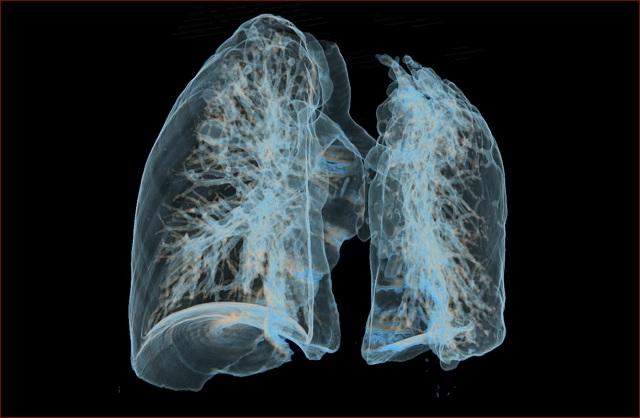

结核菌对人体具有巨大的破坏作用,特别是肺组织,可引起支气管狭窄,造成肺不张,是一部分非失去作用,严重影响肺功能,同时,肺组织别破坏排出体外后可在肺部留下空洞,有些肺部空洞不能自行闭合,会长时间的存在,洞壁上生长着很多结核菌,这种形态的病灶也是传染源之一。

结核还会留下诸多后遗症,比如支气管扩张,一旦形成,就难以根治,支气管扩张不但会造成病人长期咳嗽咳大量痰液,还会引起肺部感染,导致患者发热,严重时,支气管扩张还会导致咯血,支气管扩张和肺结核是咯血的两个最常见原因。